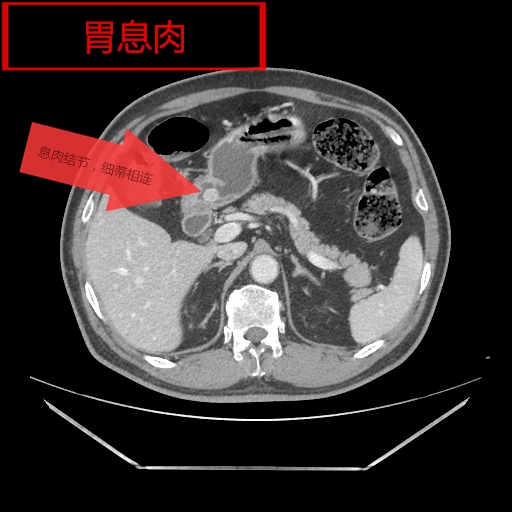

我院影像科从2018年开始,利用CT、MR分辨率高、成像方法多的特点,开展胃肠快速充盈低张CT、MR检查技术,通过多序列、多窗位、多方位检查,对肠壁、及其腔内腔外病变连续观察,取得了很好的检查诊断效果。检查技术成熟安全、无创,确诊了多例胃癌、胃息肉、结肠癌、肠先天性发育旋转不良等胃肠道疾病,并对肿瘤的转移及周围结构进行评估,为患者进一步综合治疗,打下了坚实的基础。

胶囊内镜检查具有移动的不可控性,常规消化道纤维内镜存在视野局限、有创,通过障碍无法评估腔外解剖与病变,对通过障碍的病灶仅能显示病变近端,然而胃肠道快速充盈低张影像检查技术具有无创、反复观察、定位准确的优势。它可通过充分的肠道准备,虚拟内镜及多方位重建,可从任意角度和方式对病灶进行观察,并能从狭窄、梗阻处两端观察肠腔的解剖和病变,可靠的显示了病变部位和范围,同时提供腔内外的情况并能对淋巴转移、血管癌栓、远处转移进行评估。

影像图片(一)